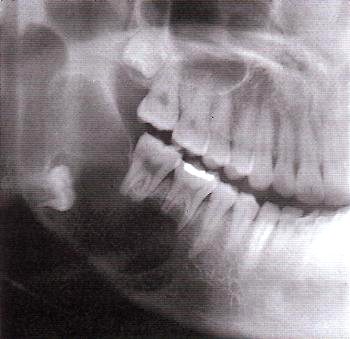

Одонтома нижней челюсти: фотографии и медицинская информация